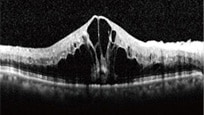

・光干渉断層計(OCT)

網膜は層構造になっており、その層構造を断面的に観察する検査です。

網膜のむくみ(黄斑浮腫)の状態がわかります。

<正常>

<網膜中心静脈閉塞症>

<網膜静脈分枝閉塞症>